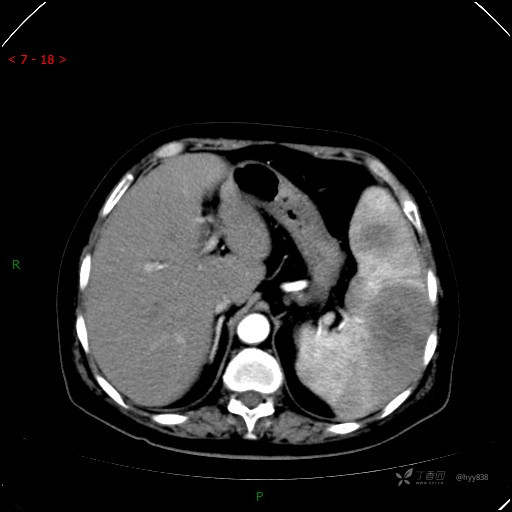

上腹部CT平扫